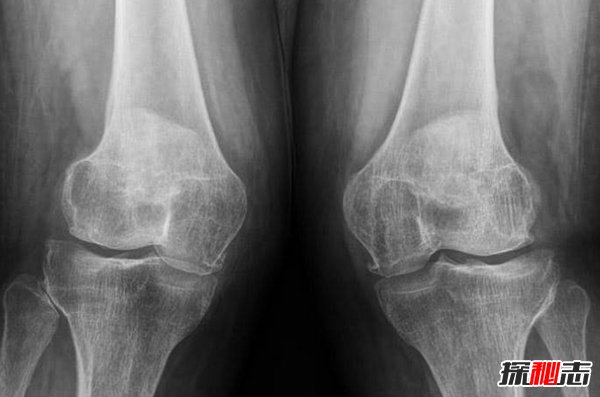

9、膝盖恐惧症

这是一个严重的问题,根据专家的说法,它可能源于先前的伤害,也可能是宗教的影响,因为某些信仰禁止膝盖被看到,强迫你跪下祈祷,乞求宽恕。